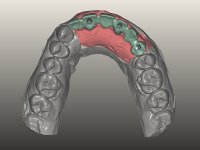

O paciente foi observado conjuntamente e a dúvida que surgiu de imediato foi se seria possível com a regeneração óssea a efectuar poder ser reabilitada naturalmente a zona das papilas interdentárias. Nesse sentido foi feito um enceramento de diagnóstico que contemplaria as duas hipóteses, utilizando ou não a cerâmica gengival. A confecção desse enceramento foi fundamental para expor ao paciente a dificuldade da reabilitação. O wax-up deu origem a um mock-up que foi aprovado pelo paciente e que simultaneamente serviu de guia imagiológica. O caso foi planificado cirurgicamente e realizada uma guia cirúrgica com que foram colocados os implantes. Após 10 semanas foi feita a 1ª impressão para confecção da ponte provisória. Foram criados os primeiros perfis de emergência na gengiva artificial e foi digitalizado o modelo. Por processo de CAD-CAM foi confeccionada uma ponte provisória aparafusada baseada no enceramento de diagnóstico. A ponte trabalhou durante 8 semanas os tecidos moles que foram fielmente copiados numa impressão com técnica de moldeira aberta. Os transferes foram individualizados com resina composta para copiarem fielmente os perfis de emergência criados pela ponte provisória. Confeccionado o modelo de trabalho definitivo, foi realizada uma infra-estrutura em zircónio seguindo a orientação do enceramento de diagnóstico. O assentamento da infra-estrutura foi testado em boca e simultaneamente foi novamente impressionados os tecidos moles com um silicone fluido. Nessa consulta foi feito o levantamento da cor. Os dentes 13 e 23 apresentavam uma saturação anormalmente forte que resolvemos não valorizar, optando por privilegiar a relação com o sector antero-inferior. Foi realizada uma nova gengiva artificial com a impressão que acompanhou a impressão de arrasto com a infra-estrutura. Após a colocação da cerâmica na infra-estrutura foram coladas as meso-estruturas. O trabalho final foi aparafusado lentamente permitindo a adaptação dos tecidos moles.